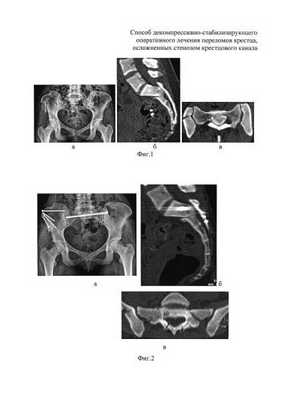

Клинический пример. Пациентка М., 21 год, поступила в клинику через 1,5 месяца после ДТП с диагнозом: ротационно-нестабильное повреждение таза; U-образный перелом крестца с вершиной над SII. Оскольчатый перелом крыла правой подвздошной кости с частичным повреждением правого крестцово-подвздошного сочленения. Радикулопатия S1 справа, S2, S3 с обеих сторон средней степени (Фиг. 1 - обзорная рентгенограмма таза (а); КТ сканы в сагиттальной (б) и горизонтальной (в) плоскости при поступлении).

По предлагаемому способу в одну операционную сессию выполнен:

- остеосинтез крыла подвздошной кости винтами и фиксация U-образного перелома крестца илиосакральным винтом для стабилизации повреждений тазовых костей;

- костнопластическая остеотомия задней стенки крестцового канала, открытая декомпрессия дурального мешка, ремоделирование крестцового канала;

- фиксация ламинектомированного фрагмента по линии остеотомии сетчатой пластиной (Фиг. 2 - представлена обзорная рентгенограмма таза (а) и КТ сканы в сагиттальной (б) и горизонтальной (в) плоскости после операции. После операции пациентка активизирована на третьи сутки, рана заживлена первичным натяжением, швы сняты не 12 сутки. Проводилась медикаментозная и электоронейростимуляция. Выписана из стационара на 17 сутки после операции.